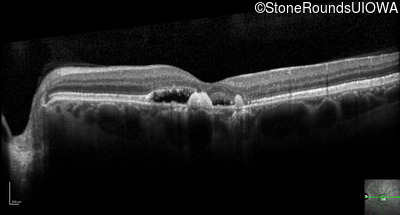

Optical Coherence Tomography - Left - 20/125 -2

Exemplar / OCT Stack